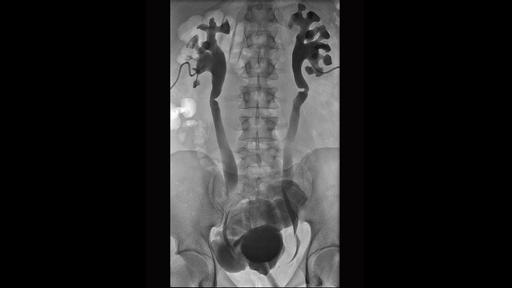

Retrograde ureterography performed for evaluation of ureteral ...

Retrograde ureterogram. | Download Scientific Diagram

Retrograde CT ureterogram. a Contrast media reached left proximal ...

Retrograde ureterogram showing the compressed ureter. | Download ...

Fluoroscopic image of a positive contrast retrograde ureterogram. The ...

Retrograde ureterography, image with no digital subtraction, frontal ...